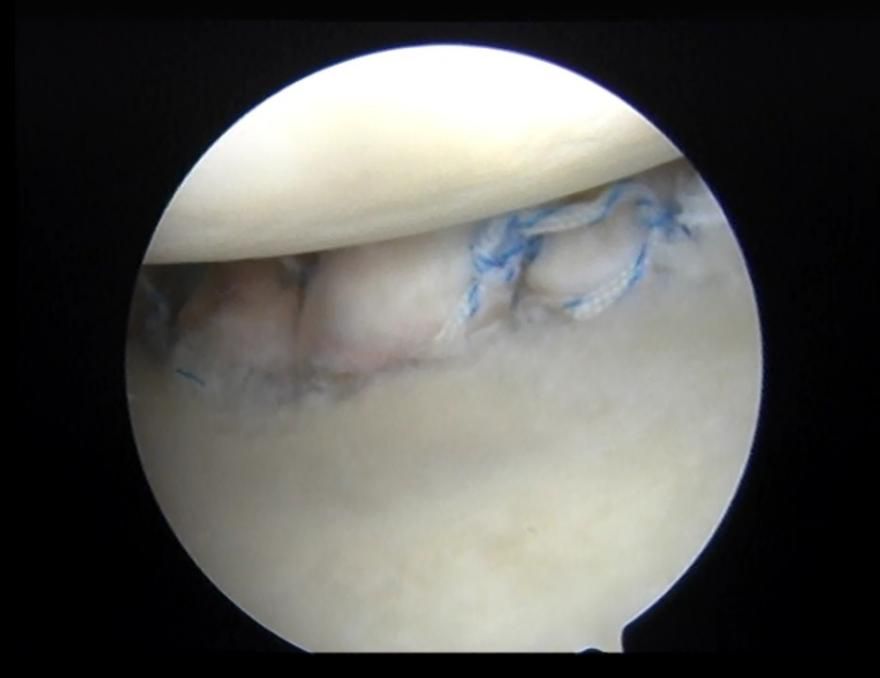

肩关节镜下修复Bankart损伤

肩关节镜下缝合修复Bony-Bankart术后